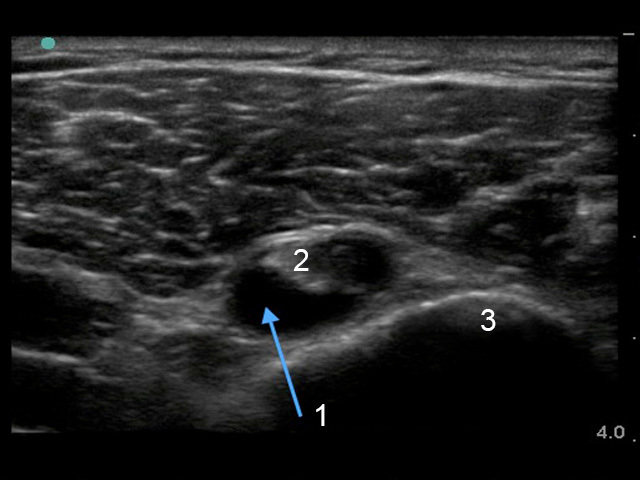

Imagen de derrame de vaina de tendón de bíceps del hombro

1. Derrame de vaina de tendón del bíceps

2. Tendón bíceps

3. Húmero